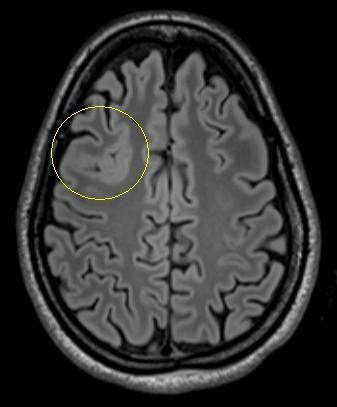

Es handelt sich um ein bildgebendes Verfahren, bei dem die Patienten in einer Röhre liegen und währenddessen mit Hilfe von wechselnden Magnetfeldern nach einem speziellen Epilepsie-Protokoll Bilder des Gehirns gemacht werden. So können Tumoren, Fehlbildungen oder andere Veränderungen des Gehirns, die Anfälle verursachen können, sichtbar gemacht werden. Durch moderne computergesteuerte Nachbearbeitungsmethoden oder Überlagerung mit anderen Bildmodalitäten können Läsionen dann noch besser dargestellt werden.

Folgende Veränderungen oder Erkrankungen des Gehirns werden häufig und mit gutem Erfolg (70-80% Anfallsfreiheit) epilepsiechirurgisch behandelt:

Tumoren

Hippocampussklerose

Fokale

cortikale Dysplasie

Umschriebene Fehlbildungen der Hirnrinde